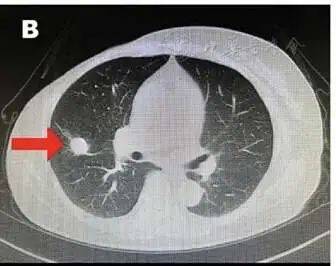

2021年9月,命运再次给我一击——PET-CT显示右肺转移。穿刺病理显示,这次的肿瘤分化较差,且有神经内分泌分化倾向,这意味着它的侵袭性更强。

图2 CT示右肺中叶转移灶

最让我无助的,是对未来治疗之路的未知与迷茫。化疗?靶向?还是免疫治疗?每一个选择都像在赌明天。最后我选择相信医生,相信自己。

面对乳腺癌肺转移,医生给我调整了治疗方案,改用内分泌治疗药物为氟维司群,加用哌柏西利CDK4/6抑制剂靶向治疗。